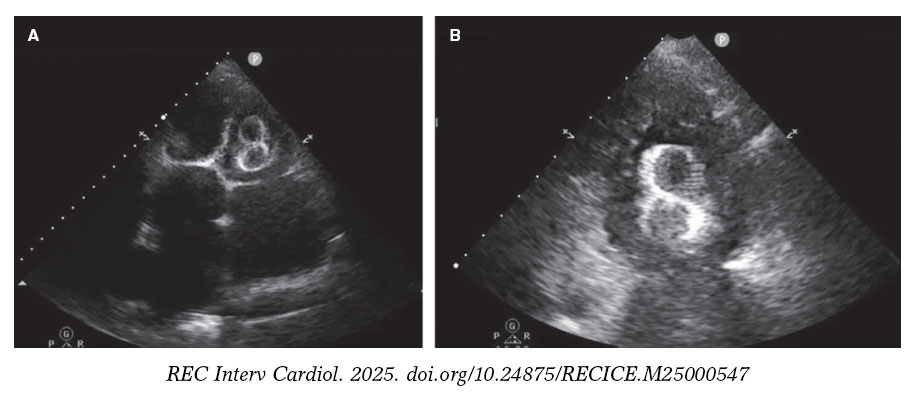

Figure 5 and figure 6 illustrate examples of left atrial appendage device embolization.

Figure 6. Transthoracic echocardiogram (TTE) performed 24 hours after implantation of a 38-mm LAmbre device. A: migration to the left ventricle (LV), with entrapment in the mitral subvalvular apparatus. B: magnified image.